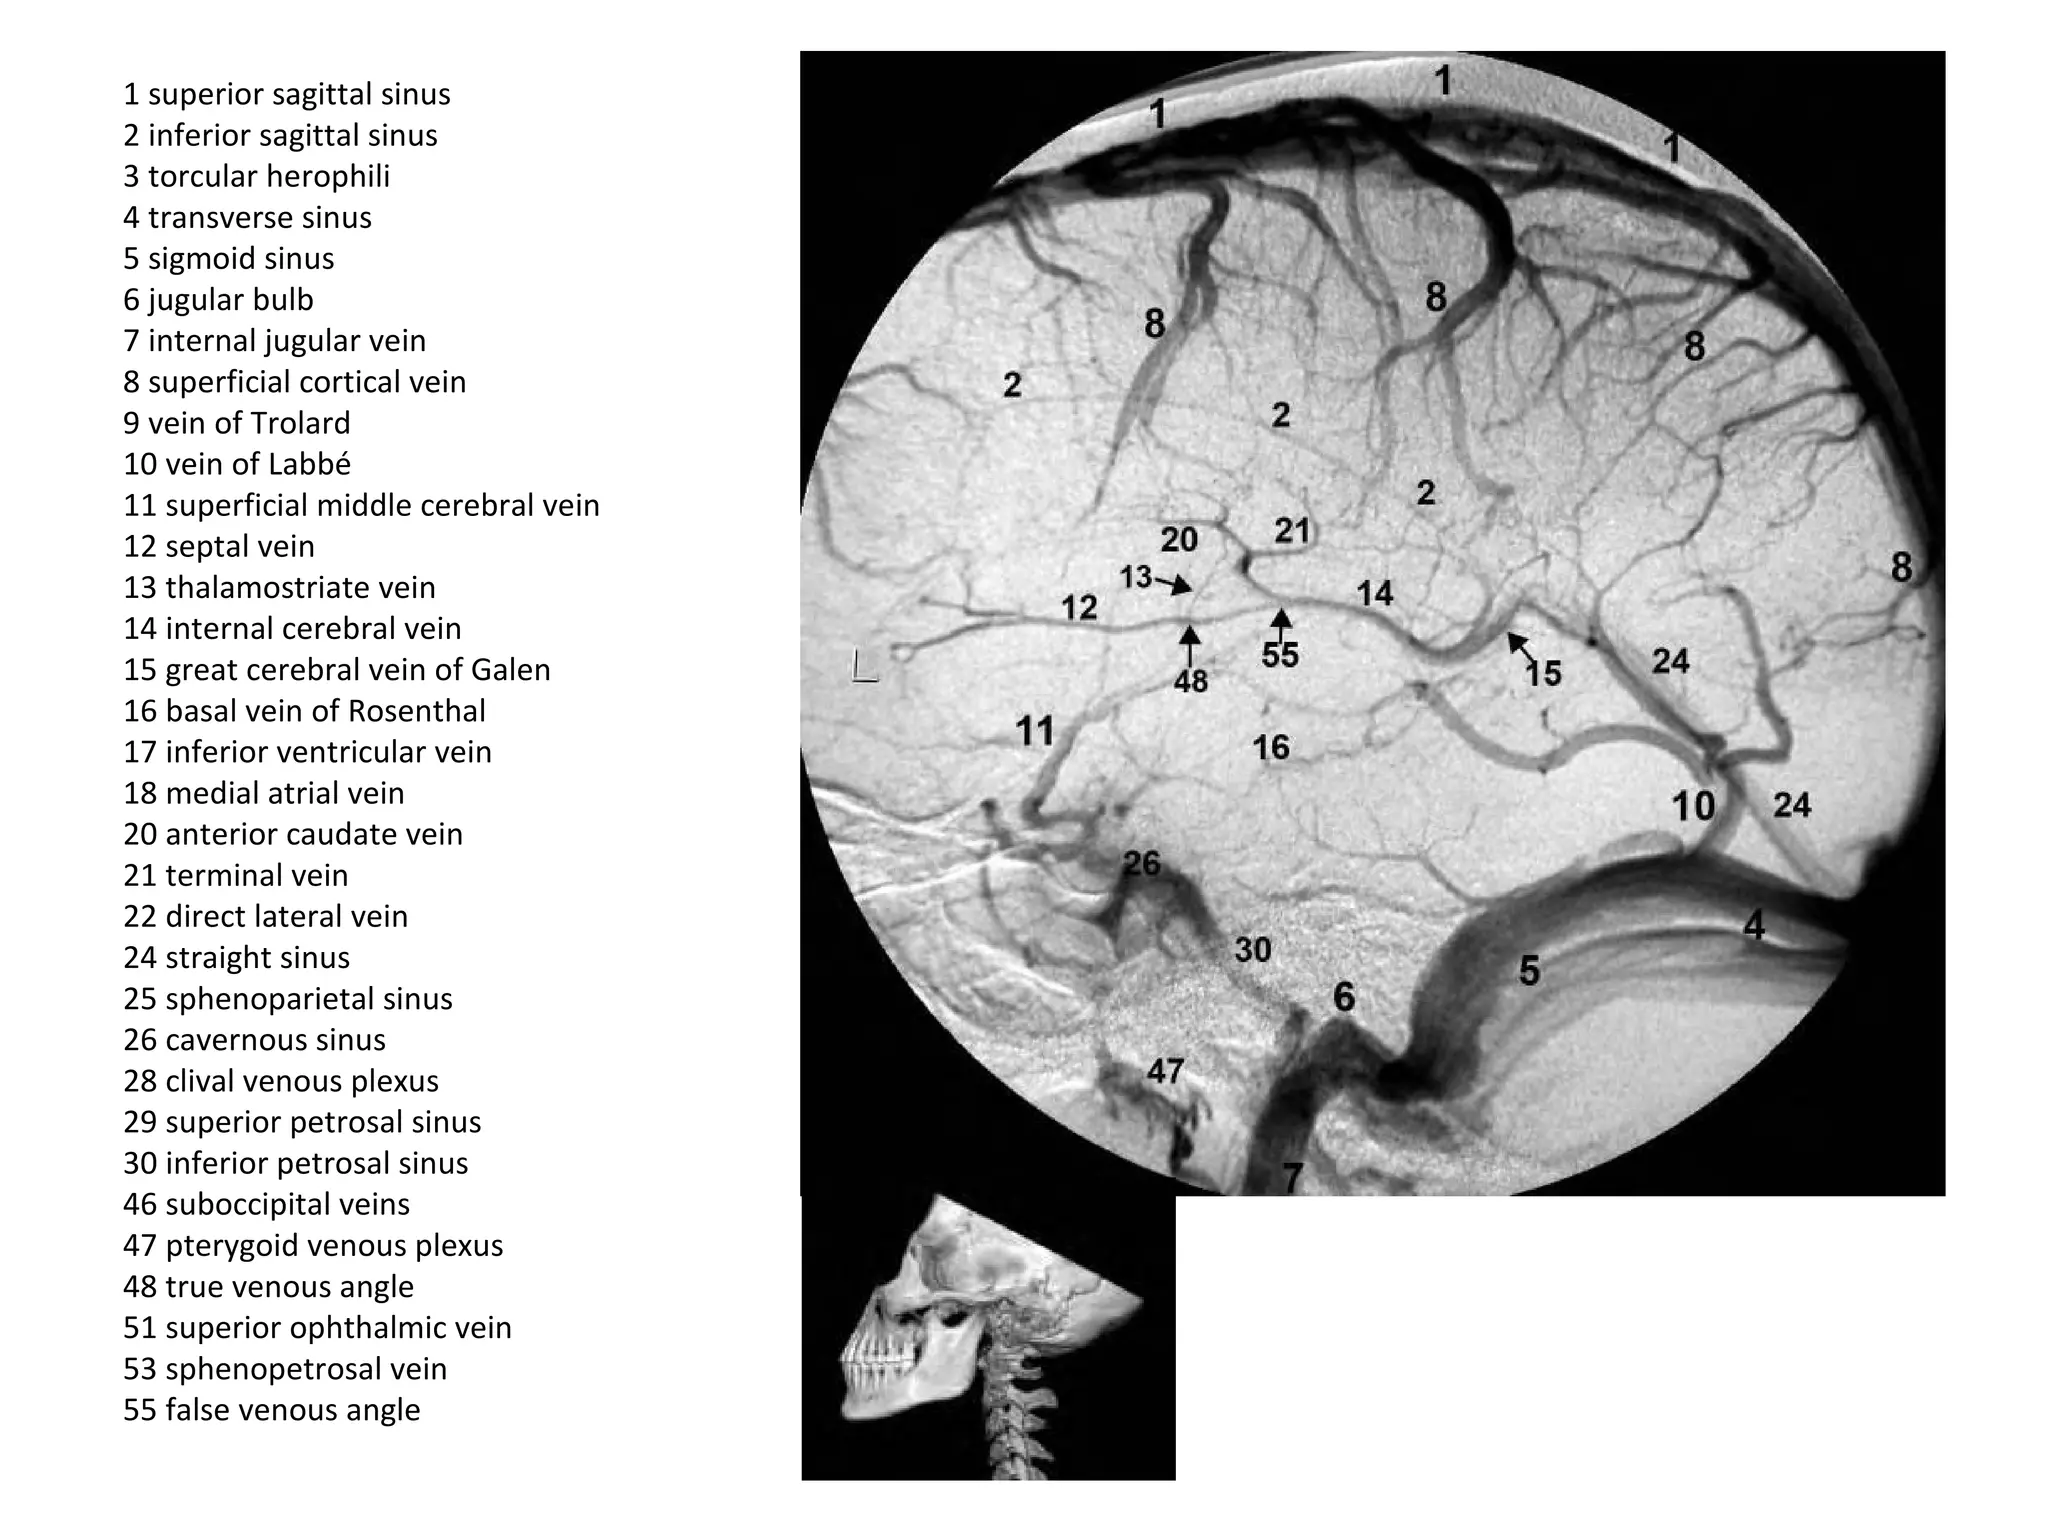

1 superior sagittal sinus

2 inferior sagittal sinus

3 torcular herophili

4 transverse sinus

5 sigmoid sinus

6 jugular bulb

7 internal jugular vein

8 superficial cortical vein

9 vein of Trolard

10 vein of Labbé

11 superficial middle cerebral vein

12 septal vein

13 thalamostriate vein

14 internal cerebral vein

15 great cerebral vein of Galen

16 basal vein of Rosenthal

17 inferior ventricular vein

18 medial atrial vein

20 anterior caudate vein

21 terminal vein

22 direct lateral vein

24 straight sinus

25 sphenoparietal sinus

26 cavernous sinus

28 clival venous plexus

29 superior petrosal sinus

30 inferior petrosal sinus

46 suboccipital veins

47 pterygoid venous plexus

48 true venous angle

51 superior ophthalmic vein

53 sphenopetrosal vein

55 false venous angle

b) Deep Cerebral Veins :

-Consist of paired internal cerebral veins , the

basal vein of Rosenthal & the vein of Galen

-The venous angle is the intersection of the

septal vein & the thalamostriate veins , the

venous angle is the angiographic mark for the

foramen of Monro